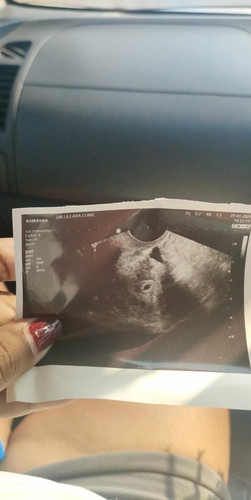

ซาวด์3สัปดาห์ เป็นแบบนี้ หมอบอกอยู่ในมดลูก แม่ๆๆคนไหนเคยเจอแบบนี้บ้างค่ะ แอบกังวนเพราะท้องแรกหยุดการเติบโตตอน6สัปดาห์

บ้านนี้ซาวครั้งแรก น่าจะ3-4วีคเจอเล็กกว่าแม่อีกค่ะ ซาวรอบ2 น่าจะ6วีคน้องก็มีหัวใจเลย